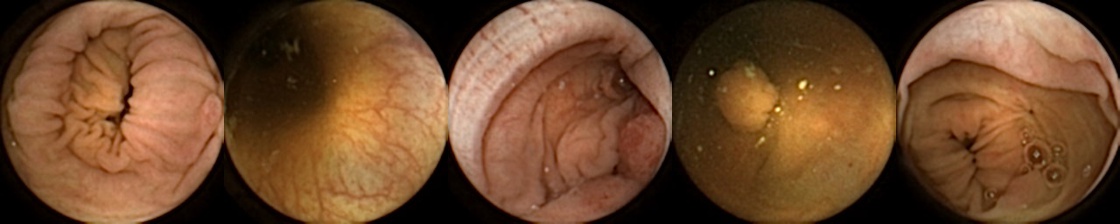

The data used in our study is based on the CareForColon2015 [kaalby2020colon, baatrup2025choice] trial conducted in the Danish colorectal cancer screening programme, which used the PillCam™ Colon 2 (Medtronic, USA) [Negreanu2013] camera capsule. We have access to 2,780 polyps from 853 patients from the CareForColon2015 study for which clinicians from the Department of Surgery of Odense University Hospital have exported up to five images per polyp. These five images correspond to 1) first partial, 2) first full, 3) best full, 4) last full, and 5) last partial image of the same polyp. This means that image 1 and 5 might just partially show the polyp. These are images from the same passing, so we know that there are no cases of the same polyp being seen at a significant later passage time. When we restrict the set to those polyps that the clinicians were able to export all these five images, we end up with 1912 polyps from 754 patients. These include 263 patients with one polyp, 204 patients with 2 polyps, 113 patients with 3 polyps, 77 patients with 4 polyps, and the rest with 5 or more polyps. Each set of five images from a polyp is given a unique patient ID and a unique polyp number.

Refer to caption

Figure 1: Positive exemplar images with each row showing five images of a unique polyp, where in each row, the first image corresponds to first partial and fifth image is the last full view of the same polyp. The polyps have been marked in green for each image.

For MIV, we construct both positive and negative exemplar pairs from this multi-patient polyp image dataset. Positive exemplars are constructed based on the five images from a single polyp, with one of the second, third, or fourth image designated as the query and the remaining four images forming the target bag. Images from five example polyps are shown in Figure 1. Negative exemplars are constructed using a more sophisticated strategy: if a patient has multiple polyps, the query image is selected from one of those polyps at random, while target images are sampled from other polyps of the same patient; if a patient has only one polyp, target images are drawn from different patients entirely.